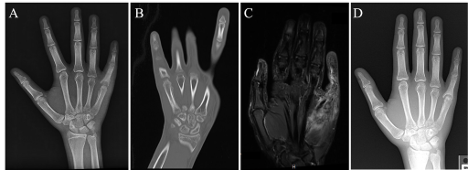

Figure. Imaging of the right hand: (A) preoperative X-ray at 2 months post-injury, (B) computed tomography at 3 months post-injury, (C) magnetic resonance imaging at 3 months post-injury, and (D) X-ray at 5 months postoperative.

The initial X-ray performed 2 weeks after the injury showed ossifications at the medial base of the fifth proximal phalanx, found to be indeterminate of overlapping osseous structures or a minor fracture. Four months after the incident, a repeated X-ray demonstrated increased periosteal reaction and sclerosis along the proximal fifth phalanx with an abnormal appearance of the fifth metacarpal phalangeal joint with soft tissue edema. A chronic nonunion of a previously noted, minimally displaced ulna styloid process fracture was also seen, in addition to an obliquely healed distal right radius fracture (Figure A).

Computed tomography of the right hand showed almost complete destruction of the base of the proximal fifth phalanx with mild sparing of the volar aspect with partial destruction of the head of the fifth metacarpal with a pencil-in-cup-like deformity (Figure B).

Magnetic resonance imaging (MRI) showed destruction of the base of the fifth proximal phalanx with bone marrow edema-like signal and hyperenhancement, suggesting osteomyelitis with infiltration of the inflammatory/infectious process of the fifth metacarpal with fifth metacarpal joint septic arthritis. The surrounding soft tissue and muscle edema also suggested cellulitis and myositis (Figure C).

After receiving the PCR results, the patient was prescribed a 30-day course of ciprofloxacin to address concern for Pseudomonas in addition to other concurrent infection etiologies. At the 5-month postoperative follow-up, the patient reported no pain and demonstrated appropriate healing; imaging showed progressive periosteal bone formation (Figure D). The pencil-in-cup deformity of the right fifth metacarpal-phalangeal joint was unchanged, the joint spaces were maintained, and the soft tissues were well preserved, indicative of healing. The patient was advised to continue physical therapy to work on passive and active range of motion (as tolerated) and to use a splint as needed for comfort. Considerations for future treatment include arthroplasty or fusion with or without joint denervation.